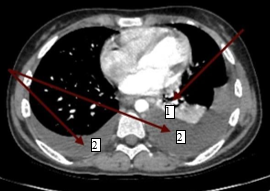

Было проведено лечение: инфузионная, антибактериальная (амклав, цефипим+сульбактам, амоксициллин), противогрибковая, обезболивающая, антигипертензивная, антисекреторная, эрадикационная, диуретическая, противорвотная, гемостатическая терапия. На фоне лечения состояние ребенка оставалось нестабильным, отмечалось неоднократное ухудшение – снижение сатурации кислорода до 86%, слабость, тошнота, периодически рвота, боли в животе опоясывающего характера с иррадиацией в поясницу, боли в паховой области, отсутствие аппетита, повышение артериального давления до 130/80 мм рт. ст. По решению телемедицинской консультации ребенок был переведен в ФГБУ «Национальный медицинский исследовательский центр онкологии им Н.Н. Блохина» Минздрава, где находился 9 дней. По данным ПЭТ КТ (позитронно-эмиссионной компьютерной томографии) с туморотропными РФП – выявлена опухолевая ткань с гиперметаболической активностью 18F-ФДГ в стенках тела желудка, множественных лимфатических узлах (выше и ниже диафрагмы), по плевре с обеих сторон. Плеврит. Асцит. Выставлен диагноз: «Перстневидноклеточный рак желудка с T3bN3bM1b, метастазы в регионарные, отдаленные лимфоузлы, кости таза. Стадия опухолевого процесса: IV». Была рекомендована полихимиотерапия по месту жительства в рамках клинических рекомендаций RUSSCO по схеме FOLFOX6 с оценкой динамики через 2 блока. В детской больнице был начат 1-й курс полихимиотерапии согласно протоколу FOLFOX 6 – оксалиплатин 85 мг/м2, лейковирин 400 мг/м2, 5-фторурацил 2000 мг/м2 с проведением сопроводительной терапии. После окончания первого курса сохранялось тяжелое состояние за счет диссеминации опухолевого процесса, выраженной интоксикации, хронического болевого синдрома, дыхательной недостаточности I степени на фоне двустороннего плеврита, асцита. Температура тела повысилась до фебрильных значений, присоединился кашель. Аускультативно в лёгких дыхание стало ослабленным в нижних отделах справа и слева, выслушивались разнокалиберные хрипы с двух сторон. На КТ органов грудной клетки (рис. 4) в плевральных полостях отмечалось большое количество неоднородного содержимого, в S4, S5 левого легкого – признаки инфильтративных изменений.

Рис. 4. Компьютерная томограмма органов грудной клетки пациентки с раком желудка: инфильтративные изменения верхней доли левого легкого, более вероятно, воспалительного генеза (1); картина двустороннего гидроторакса (2)